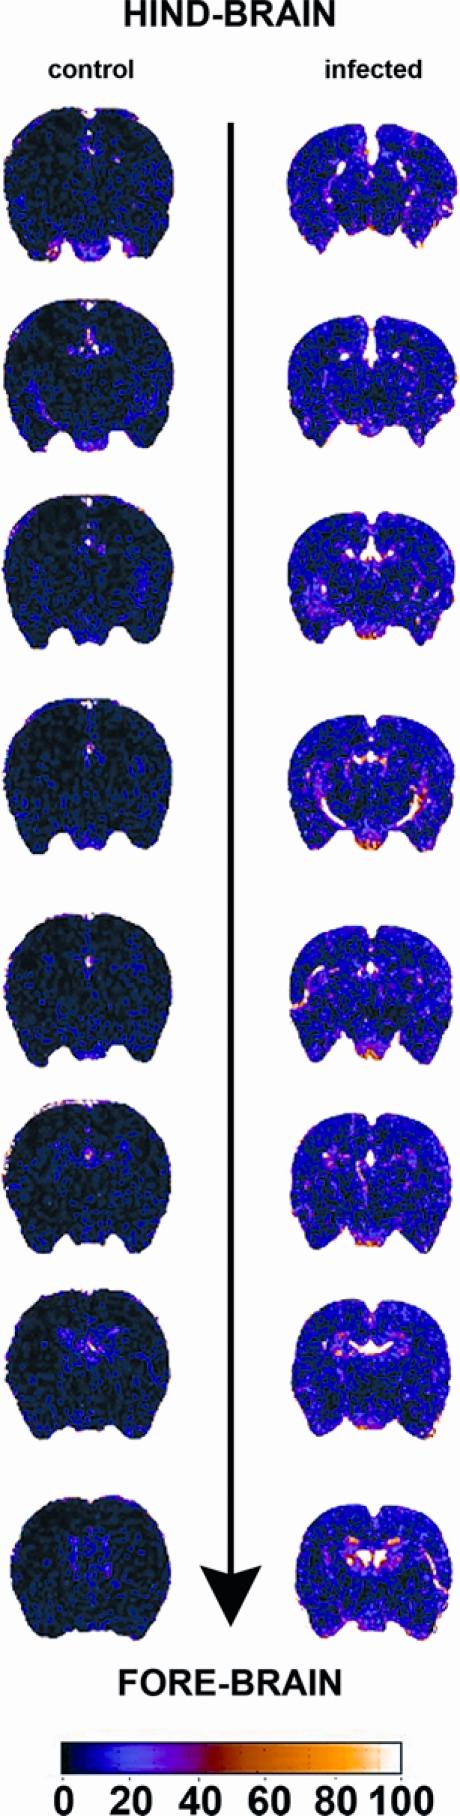

The ability of trypanosomes to invade the brain and induce an inflammatory reaction is well-recognized. This study uses magnetic resonance imaging (MRI) in conjunction with a murine model of central nervous system (CNS) stage trypanosomiasis to investigate this phenomenon at the level of the blood-brain barrier (BBB). Mice were scanned before and after administration of the contrast agent. Signal enhancement maps were generated, and the percentage signal change was calculated. The severity of the neuroinflammation was also assessed. Statistical analysis of the signal change data revealed a significantly (P = 0.028) higher signal enhancement in mice at 28 days post-infection (least squares mean = 26.709) compared with uninfected animals (6.298), indicating the presence of BBB impairment. Leukocytes were found in the meninges and perivascular space of some blood vessels in the infected mice. This study shows that the integrity of the BBB is compromised during CNS stage trypanosomiasis and that the impairment does not correlate with inflammatory cell infiltration.

锥虫侵入大脑并引发炎症反应的能力是众所周知的。本研究使用磁共振成像(MRI)结合中枢神经系统(CNS)阶段锥虫病的小鼠模型,在血脑屏障(BBB)水平上研究这一现象。在给予造影剂之前和之后对小鼠进行扫描。生成信号增强图,并计算信号变化的百分比。还评估了神经炎症的严重程度。信号变化数据的统计分析显示,感染后 28 天的小鼠(最小二乘均值= 26.709)与未感染动物(6.298)相比,信号增强显著(P = 0.028),表明存在 BBB 损伤。在感染小鼠的脑膜和一些血管的血管周围空间中发现了白细胞。这项研究表明,在中枢神经系统阶段锥虫病期间 BBB 的完整性受到损害,并且这种损害与炎症细胞浸润无关。